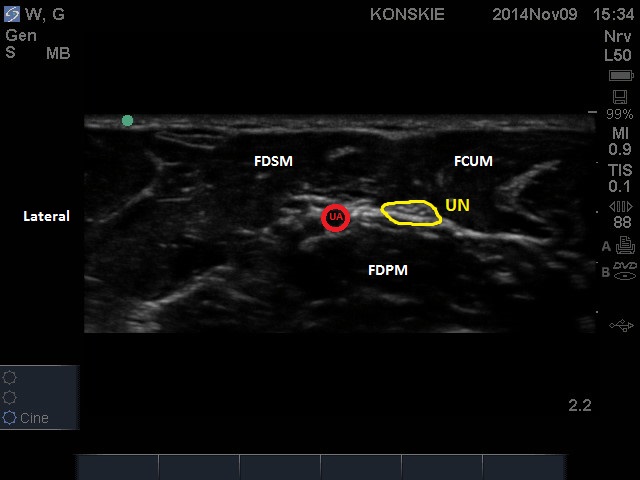

Nerw łokciowy możemy łatwo uwidocznić na poziomie przedramienia. W tym celu liniową głowicę USG przykładamy w połowie przedramienia po stronie dłoniowej, następnie kierujemy się w stronę łokciową. Nerw łokciowy, wciśnięty pomiędzy warstwę głęboką i przyśrodkową mięśni przedramienia, znajduje się bezpośrednio przyśrodkowo w stosunku do tętnicy łokciowej i przybiera kształt owalnej lub lekko wrzecionowatej hiperechogenicznej struktury. „Śledząc” nerw w kieruku proksymalnym, tętnica łokciowa odsuwa się od nerwu, natomiast w kierunku dystalnym, nerw i tętnica zbliżają się do siebie, biegnąc bardziej powierzchownie.

Na poziomie nadgarstka nerw towarzyszy tętnicy łokciowej, lecz jego lokalizacja może stwarzać duże problemy z uwagi na obecność licznych struktur ścięgnistych zbliżonych echogenicznością do nerwu.